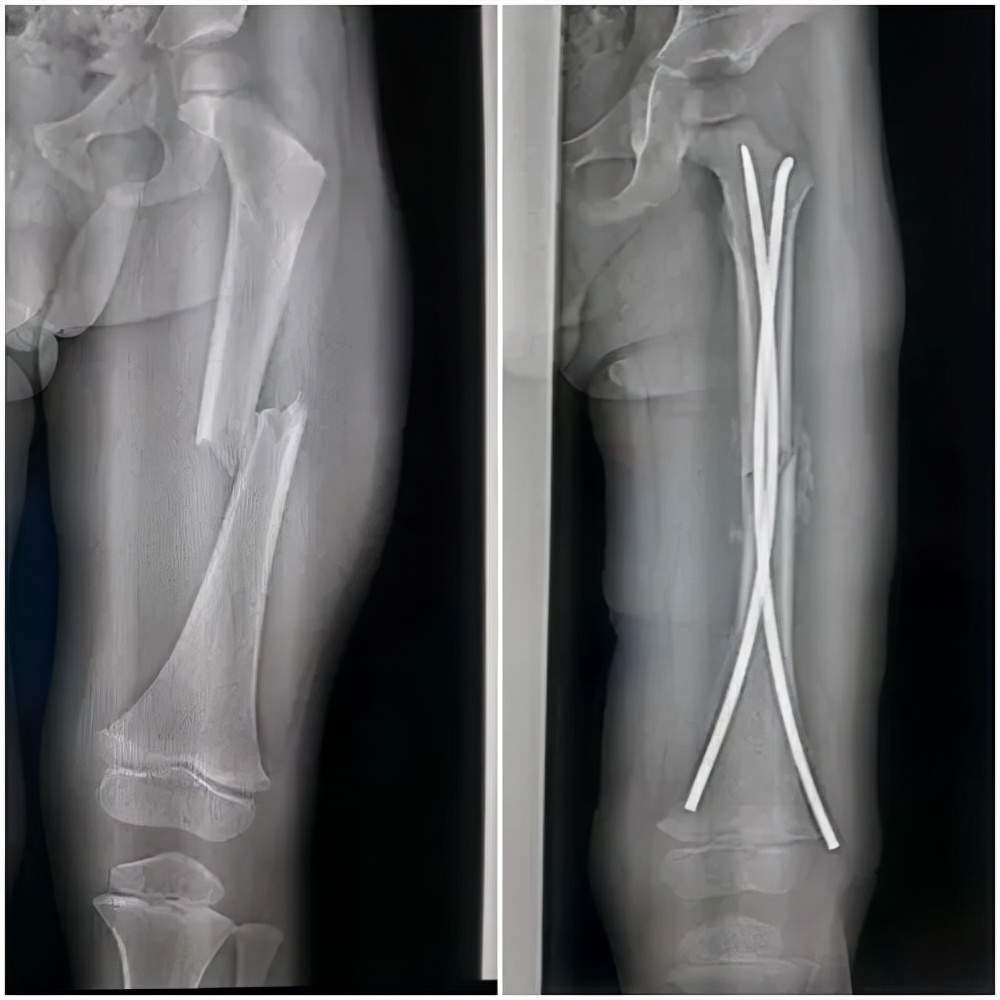

老主任还说,自己治疗儿童骨折的手术经验还停留在几十年前,他向儿童医院的骨科专家咨询了,现在治疗儿童股骨干骨折主流的手术方式是微创下弹性髓内钉固定术,切口只有2厘米左右,通过微创的方法,把固定骨折的钢钉插进去,弹性固定。

而不是采用自己以往的手术方式,切个大口子,把钢板螺钉放进去固定住,这样的手术方式,手术的切口大,对组织损伤严重,患儿术后的痛苦也大。